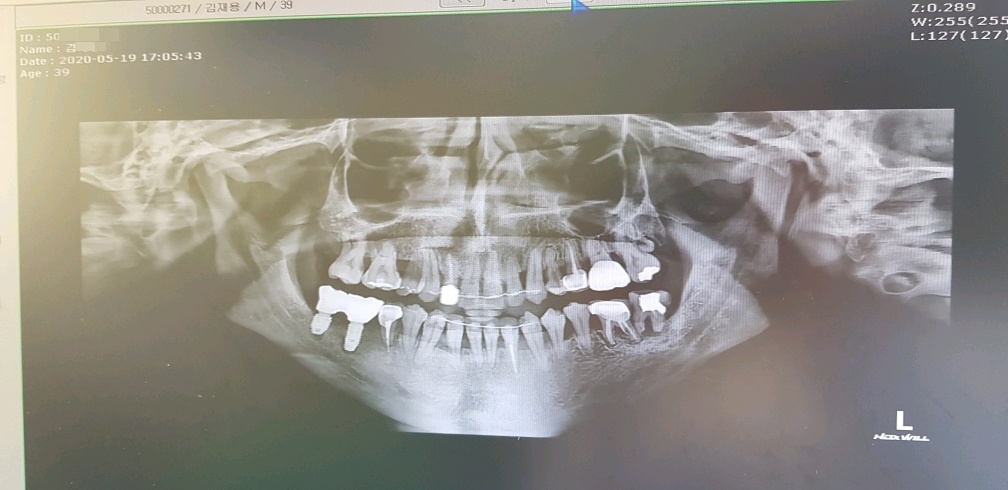

화면상에서 왼쪽치아 두개는 잘 됐다고 해서 다행인데

오른쪽 어금니 치아 두개다가 상태가 영...심각하다..

오른쪽 어금니가 저렇게 된 이유는 과거에(12년전 쯤) 사랑니가 어금니 옆쪽을 치고 나오면서

그렇게 30분 정도가 흐른 후 잘 박혔는지 엑스레이 찍고 후덜덜 한 상태로 드디어 끝났다...

잘심어진 건지는 모르겠으나.. 그냥 내가 겉보기엔 다행히도 잘 된거 같다..

근데 바로 앞의 치아뿌리가 왜저리 올라와 있는건지...;;

여기 원장님 말로는 엑스레이 보여주면서

다른 교정치과에서 치료했던 치아가 문제인것 같다 한다..

신경치료 하면서 심어놨던 하얀색(치아뿌리의 중간부분)이 치아뿌리 안쪽에만 있어야 되는데

뿌리를 넘어서서 아픈것일 수도 있다고 하고(실제로 살짝 딱딱한걸 깨물어 보면 통증이 장난아니다..)

두번째로는 화살표 표시해둔 부분 이부분이 치아뿌리 끝 부터 염증이 생겨서 아픈것 일수도 있다고 한다..